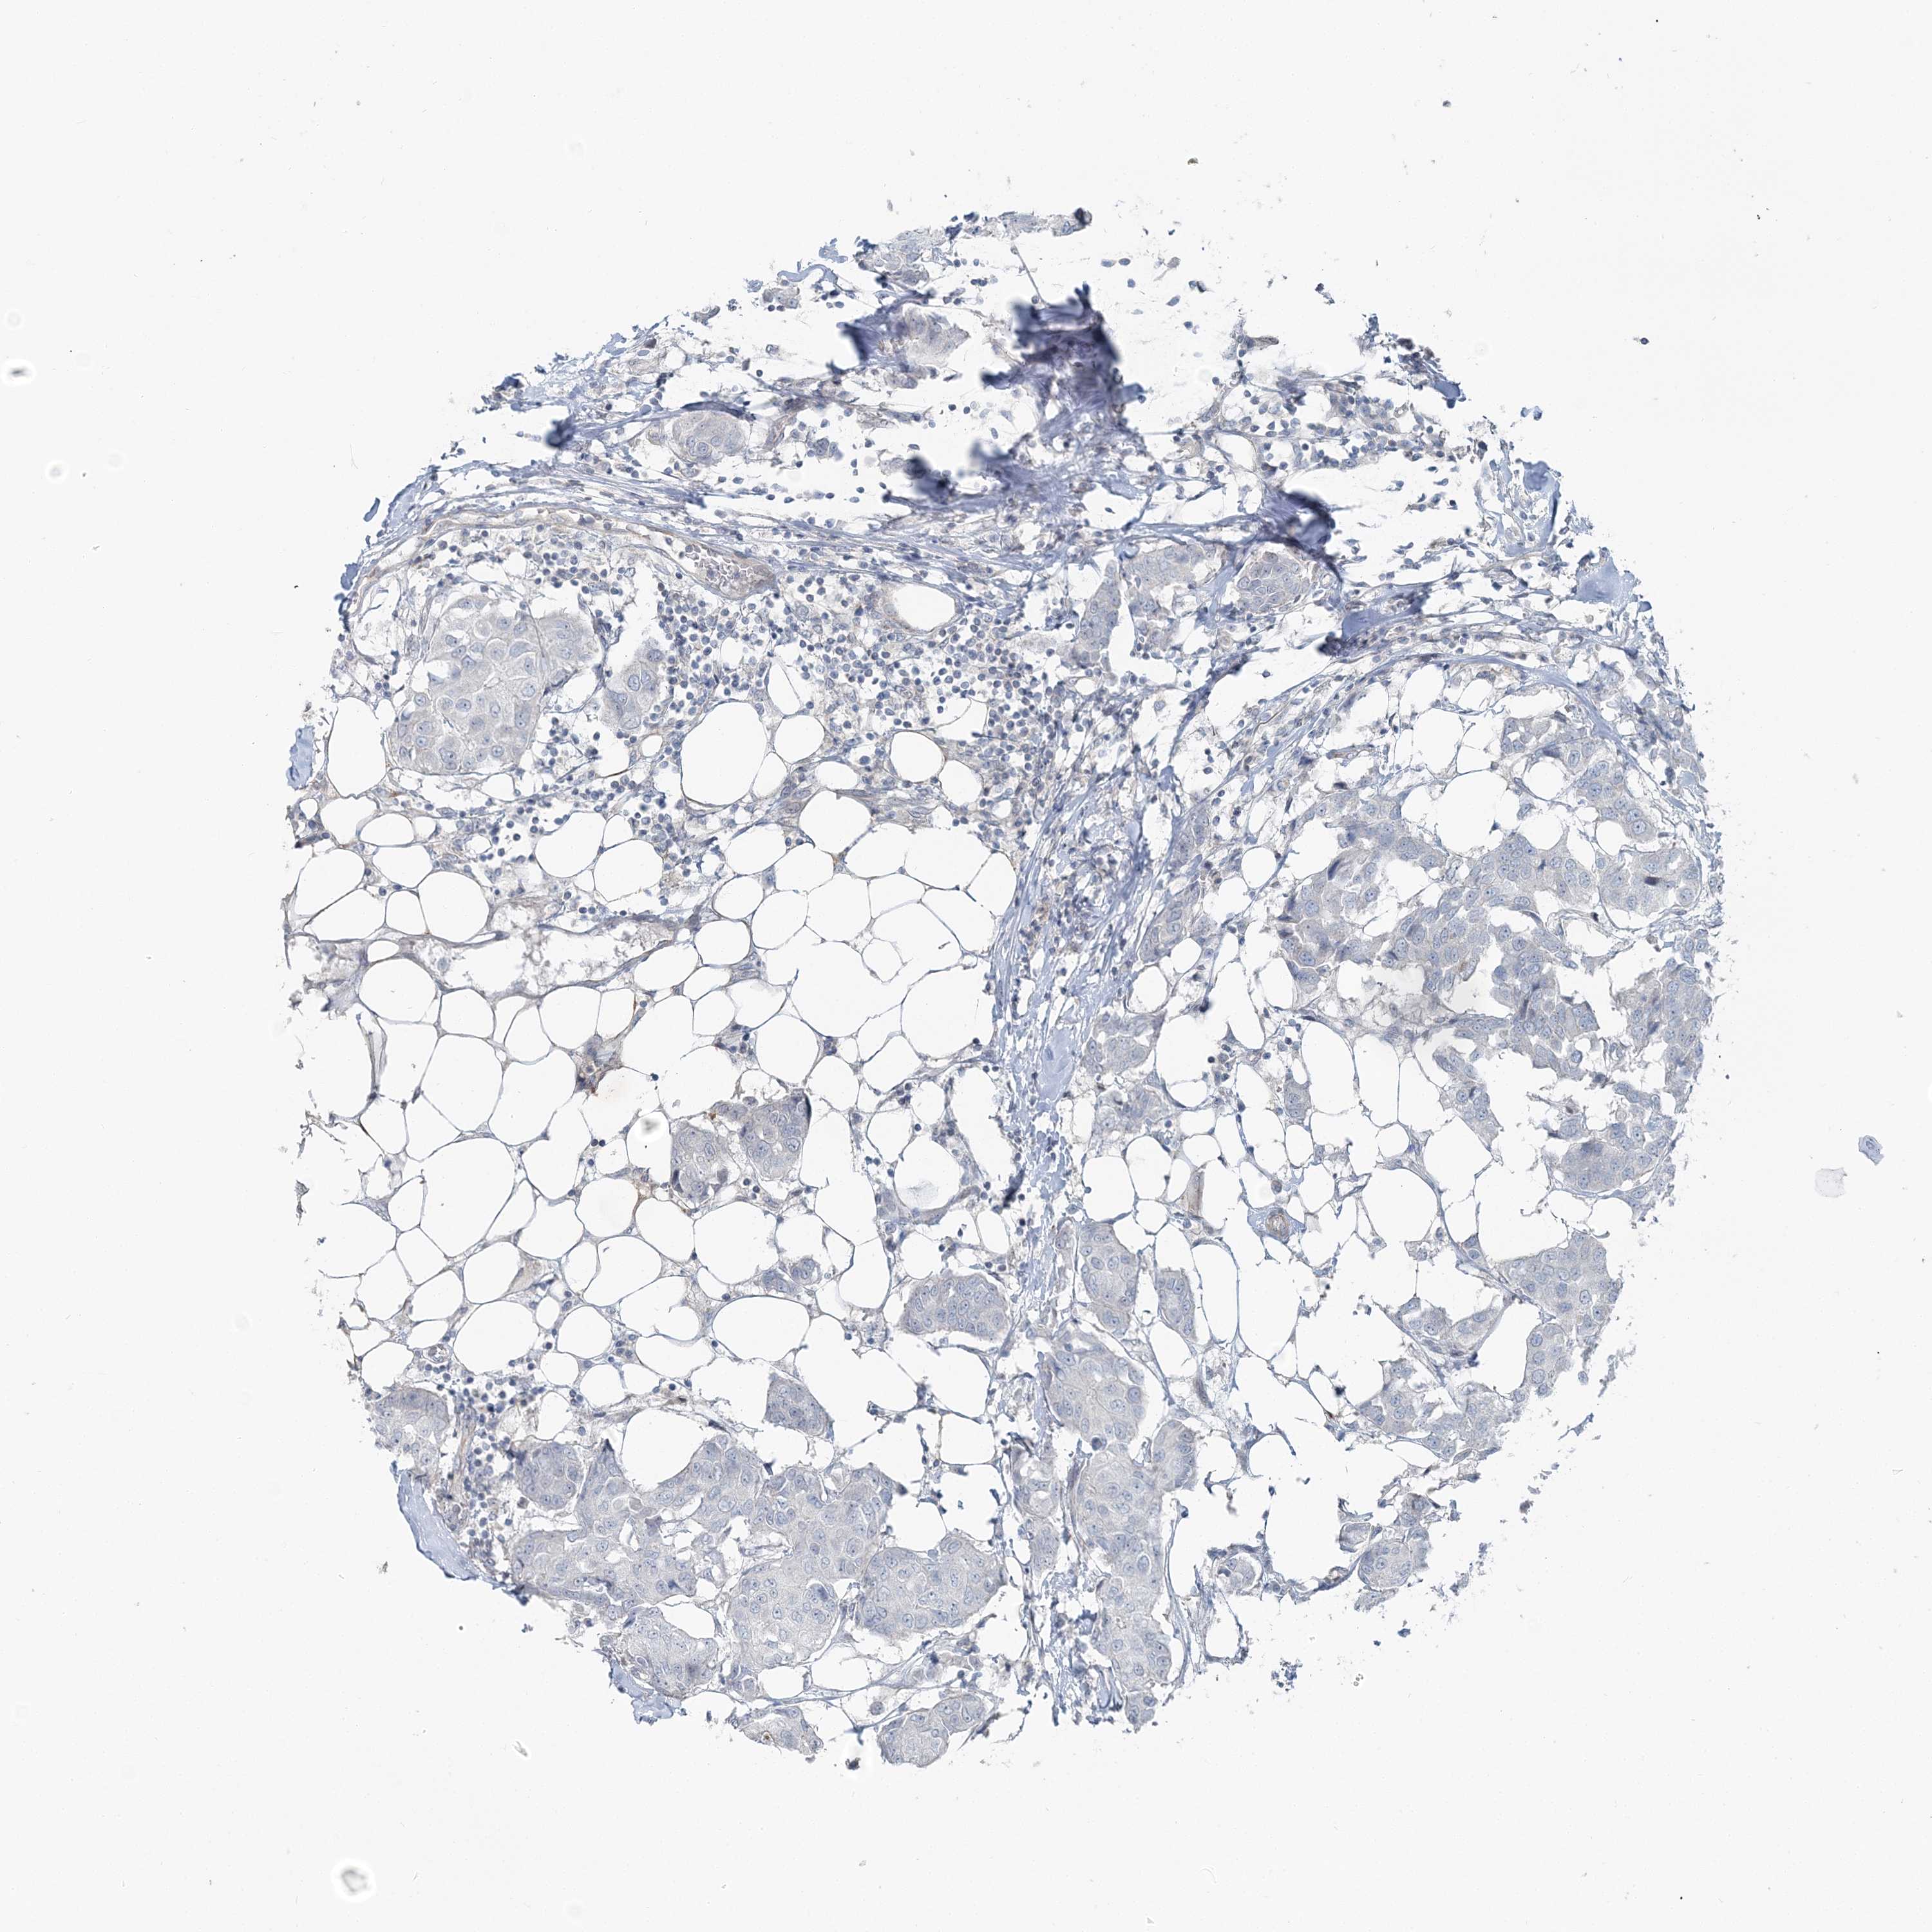

CANCER BREAST CANCER Show tissue menu

BRCA TCGA BRCA VALIDATION PROTEIN EXPRESSION